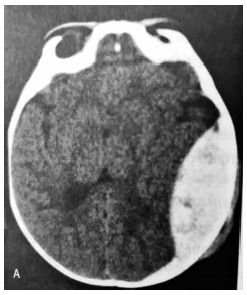

Paciente de 32 anos, masculino, admitido no pronto atendimento com história de acidente automobilístico (queda de moto), sendo atendido localmente pela equipe do SAMU. Na admissão, encontrava-se sonolento, resposta verbal inadequada, hemiparesia à direita, resposta à dor localizatória à esquerda e pupilas discretamente assimétricas (esquerda > direita). Realizou exame de tomografia de crânio (abaixo). Com base no quadro clínico e na imagem, assinale a alternativa que contempla corretamente o diagnóstico deste paciente.